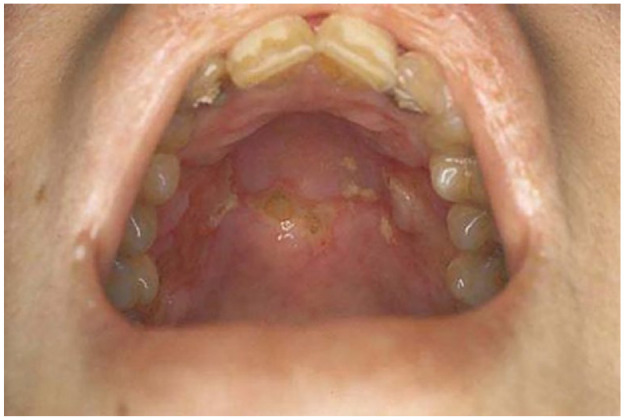

Behçet's disease is a kind of variable vessel vasculitis (VVV) and inflammatory systematic disease affecting various organs of the body. The cause of the disease is idiopathic but is most commonly genetic in origin. A positive skin prick test (dermatographia), genital sores, eye irritation, skin sores, and at least three episodes of mouth sores in a year confirm the diagnosis. Treatment may include immunosuppressive agents, immune modulators, and biological markers such as corticosteroids, immunosuppressants, and antibodies. We report a case of a 23-year-old male patient, presented in an outpatient clinic in a tertiary care eye hospital located in Pakistan. The patient reported sudden loss of vision in one eye and graduate loss of vision in the other eye. Ocular and systemic investigations were performed to correlate with clinical findings to reach a diagnosis. The patient was managed symptomatically and was put on corticosteroids. Our hospital is a research and postgraduate educational institution that deals with complex eye diseases. The range of investigations and clinical exams helped clinical decision-makers in evaluating the patient's diagnosis.